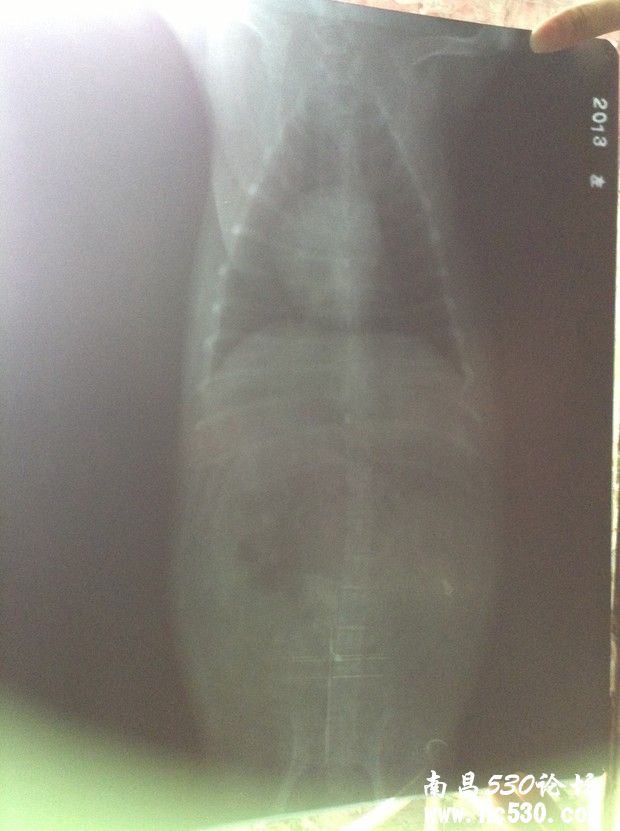

狗狗咳嗽已好几个月,之前一直是偶尔一两声卡卡干咳声,到最近转变成一连串咳嗽,明显加重,而且咳嗽声音变化了。前天带去医院看,打了X光,查了血常规和电解质(这个查没查我不知道医生也没说但收了费)。然后医生说心脏有点点肥大,应该是心脏顶到气管造成的咳嗽。别的血常规这些都正常,血压也正常。就说以后给它吃皇家心脏处方狗粮,然后开了几颗扩张支气管的药(肺心康),两三天的量。就这样了。但是狗狗回来还是一直咳,特别是晚上,咳得很可怜,咳到最后还象卡痰那样的象有痰吐不出来似的。我就是想知道,我家狗狗到底是不是因为心脏原因引起的咳嗽,还是会是别的?难道就让它这么咳下去么?皇家心脏处方狗粮现在买不到,还是吃的平常的,因为说它有点点偏胖就给它吃得很少减了量。它现在饿跑来想吃我都不敢给它吃,请问这样让它少吃的做法对么?还是吃一般的狗粮可以么?

还有就是今天回来仔细看片子,发现下图那块(喉咙还是气管那下面我圈起来的地方)有块东西,也不知道是片子是脏的还是它身上的?特意放上来请各位专家医生看看。说实话,那天医生也没和我讲清楚,连查血那些的单子也没给我,病历也未给写,片子我还是走的时候要求要的。